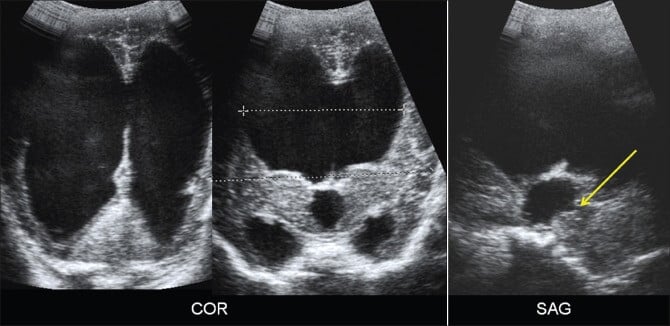

A neurossonografia começa com imagens em escala de cinza obtidas pela fontanela anterior nos planos coronal e sagital.

No plano coronal, geralmente obtêm-se de seis a oito imagens, cobrindo dos lobos frontais até os occipitais. Em seguida, rotaciona-se o transdutor 90° para capturar cinco imagens sagitais, incluindo a linha média e as regiões parasagitais de ambos os hemisférios.

Emprega-se medições específicas, como as razões biventricular e bifrontal no nível do forame de Monro, como parâmetros objetivos para o seguimento da hidrocefalia.